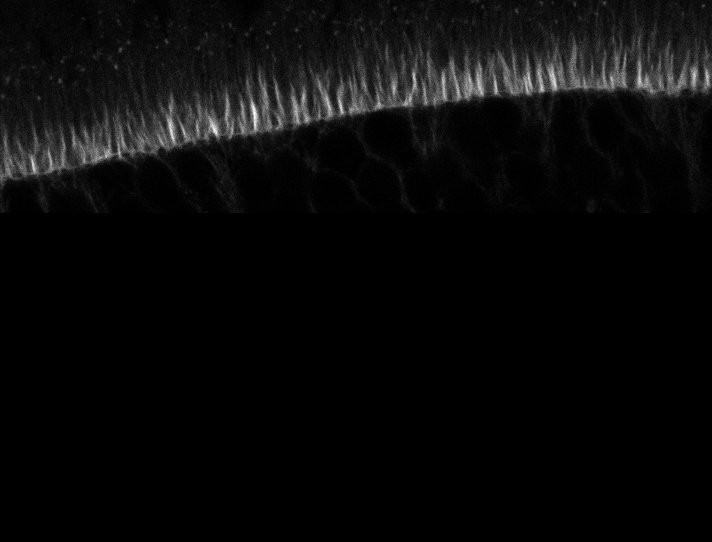

Healthy Eye

Overview 1